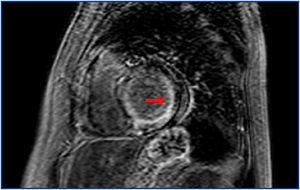

El corazón es el otro órgano mayormente implicado en la amiloidosis (figura 1). La afectación cardíaca se da en un 50 % de pacientes con amiloidosis AL. La afectación cardíaca debe sospecharse en pacientes que presentan clínica de IC principalmente derecha, con función sistólica conservada y disfunción diastólica3. El edema pulmonar no es común. El daño miocárdico establecido se evalúa con la determinación de troponinas y péptido natriurético atrial, que pueden utilizarse en la monitorización del tratamiento. Para el diagnóstico de amiloidosis se requiere una biopsia positiva para la tinción de rojo congo en un tejido y, si existe sospecha de afectación cardíaca, una prueba de imagen cardíaca compatible (ecocardiograma o resonancia magnética), o bien la biopsia endomiocárdica, que es un procedimiento relativamente seguro en manos expertas1,5.

Figura 1. Resonancia magnética cardíaca. Imagen de realce tardío de gadolinio en subendocardio